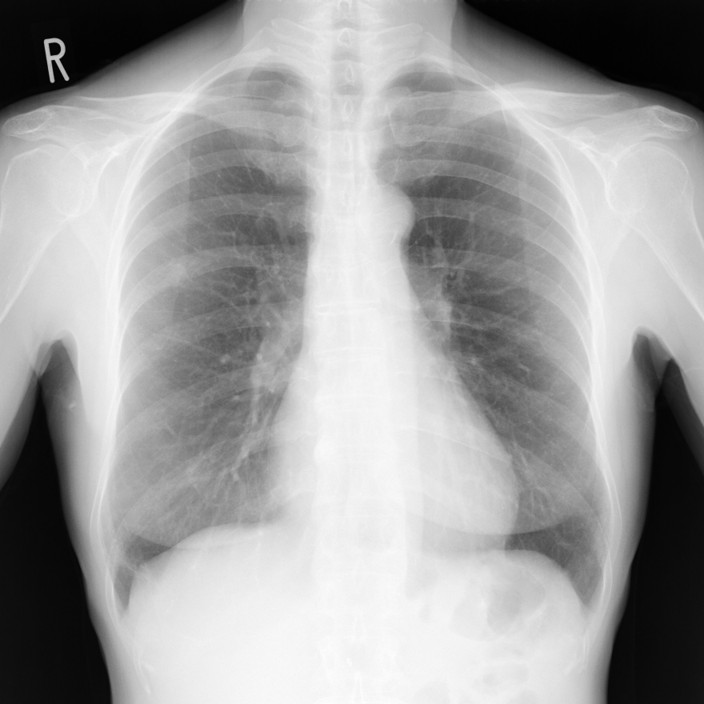

一番身近な検査「レントゲン写真」

画像検査と聞いて、皆さんが一番に思い浮かべるのは「レントゲン(胸部X線検査)写真」だと思います。

学校の健康診断や会社の人間ドックでも必ずと言っていいほど行われる、非常にポピュラーな検査です。

レントゲン検査の仕組みは、一言で言えば「影絵」と同じです。

体の後ろからX線を当てて、通り抜けてきた光を、胸側に設置したセンサーで受け取ります。

レントゲン検査では、水分や骨のようにX線を通しにくい部分は白く、空気のようにX線を通しにくい部分は黒く写ります。

呼吸器症状の診断では、レントゲン検査は「最初の窓口」として極めて重要な役割を果たします。

特別な準備もなく撮影は一瞬で終わり、放射線量も極めて少なく(日常生活で自然界から受けている放射線量と比べても無視できるほどわずか)、パッと非常に簡単に行える検査ですので、肺全体の大まかな状態を把握するのに最適だからです。